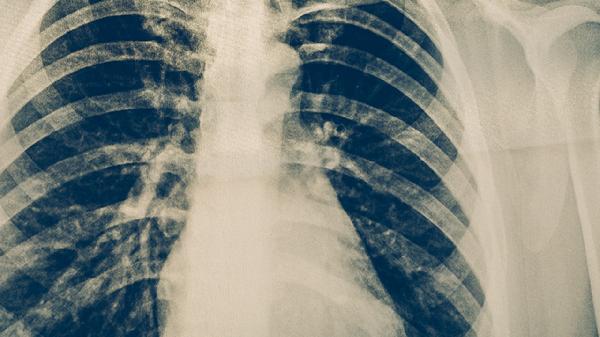

双肺间质性肺炎的治疗方法主要有氧疗、糖皮质激素治疗、免疫抑制剂治疗、抗纤维化药物治疗和肺康复训练。双肺间质性肺炎可能与感染、自身免疫性疾病、环境暴露等因素有关,通常表现为呼吸困难、干咳、乏力等症状。